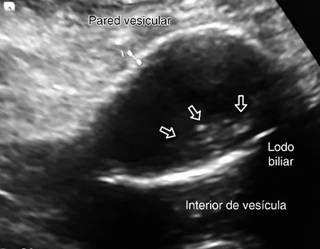

Figura 2: Ultrasonido abdominal, se observa línea ecogénica única que corresponde a la pared vesicular calcificada y presencia de “lodo biliar” (flechas).